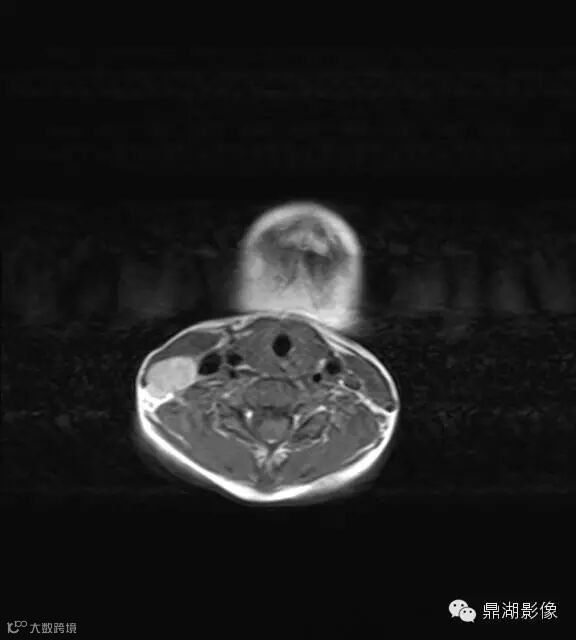

病史:男,5岁,发烧起病 39.5,咽痛,扁桃体II度,家属发现颈部肿块,质地硬,压痛。

上海儿童医院韩燕乔教授诊断:考虑淋巴结炎 ,可见杯状分层,液液平

出院临床诊断:上呼吸道支原体感染,淋巴结炎